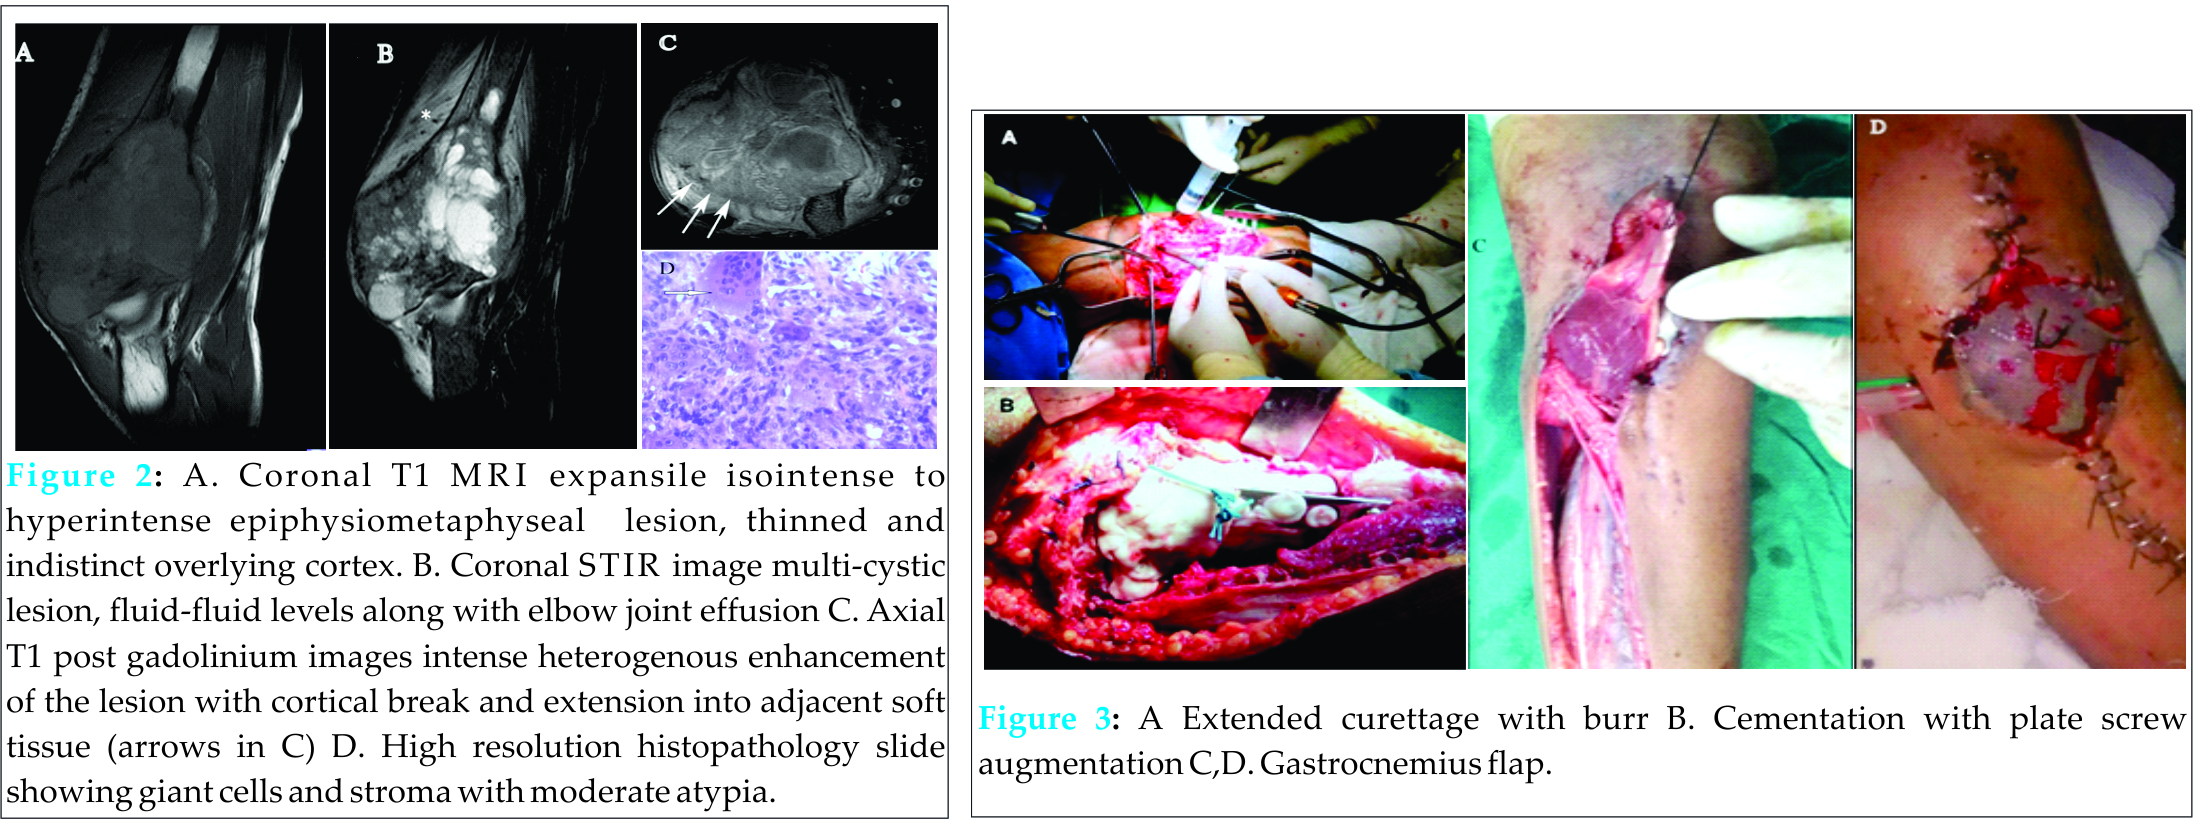

In our orthopaedic oncology clinic we have come across two pediatric patients having giant cell tumor of bone in last two years. First patient was a 15 years old male child presenting to us with history of pain, swelling in right distal humerus for last three months. Second patient was thirteen years old male who came with a history of swelling proximal tibia and painful ambulation for last four months. Their detailed clinicopathological profile is given in Table 1. There was no antecedent history of trauma or systemic disease. Radiologically features of epiphyseometaphyseal lesion, thinned out cortices, physeal destruction and wide zone of transition were noted more so in first patient. Keeping in view age of patients and radiological appearance differential diagnosis- of chondroblastoma, brown tumor, aneurysmal bone cyst and giant cell tumor were kept. Biochemical profile revealed normal serum alkaline phosphatase levels thereby excluding hyperparathyroidism. MRI in both patients was suggestive of GCT which was confirmed by histopathology examination.

Both patients had Campanacci grade III giant cell lesions and were managed surgically. As Case 1 had cortical breach in multiple planes, large soft tissue component, total physeal destruction, large area of subchondral bone involvement, hence wide resection with total elbow replacement was planned [Fig.1].

Case 2 had minimal cortical breach and a small soft tissue component. Hence this patient was managed by extended curettage, cementation and plate-screw construct augmentation. There was wound dehiscence at six weeks in this patient which was managed by gasrtrocnemius flap [Fig.3]. Both the patients are free of recurrence at one year follow up.